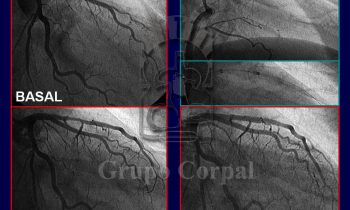

Coronariografía Selectiva en el Infarto de Miocardio

por Grupo Corpal | 1 Feb, 2017 | Blog Cardiológico, Imagen del mes

Valor de la Coronariografía Selectiva en el Infarto de Miocardio   Imágenes angiográficas de un paciente en la fase aguda de un infarto de miocardio. Basalmente, se puede ver que la arteria coronaria responsable...